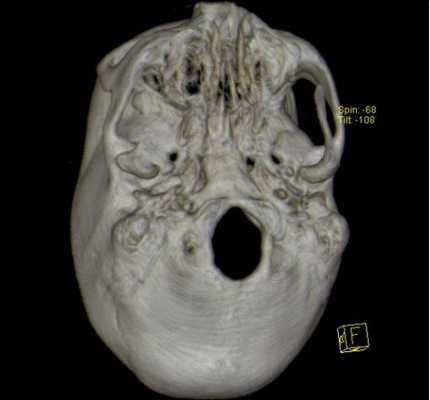

![3D-реконструкция с помощью компьютерной томографии]()

3D-реконструкция с помощью компьютерной томографии

![Трехмерные реконструкции, выполненные с помощью КТ]()

Трехмерные реконструкции, выполненные с помощью КТ